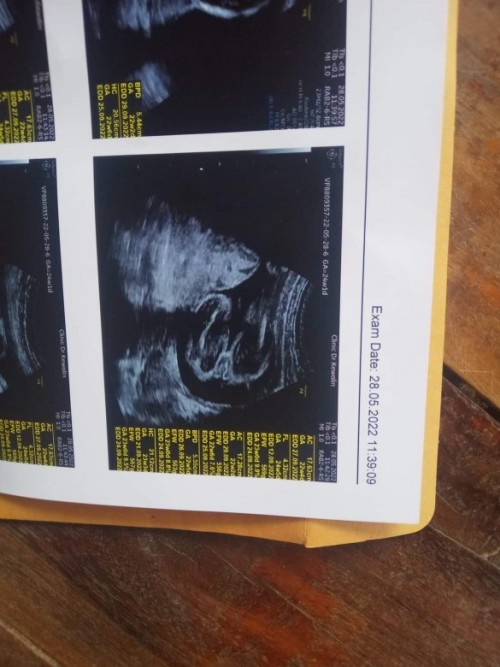

เป็นแท่งขนาดนี้ ลูกชายแน่นอนค่ะ

โด่มาเลยแม่555

ชายจ้า

ชัดเลยค่ะ